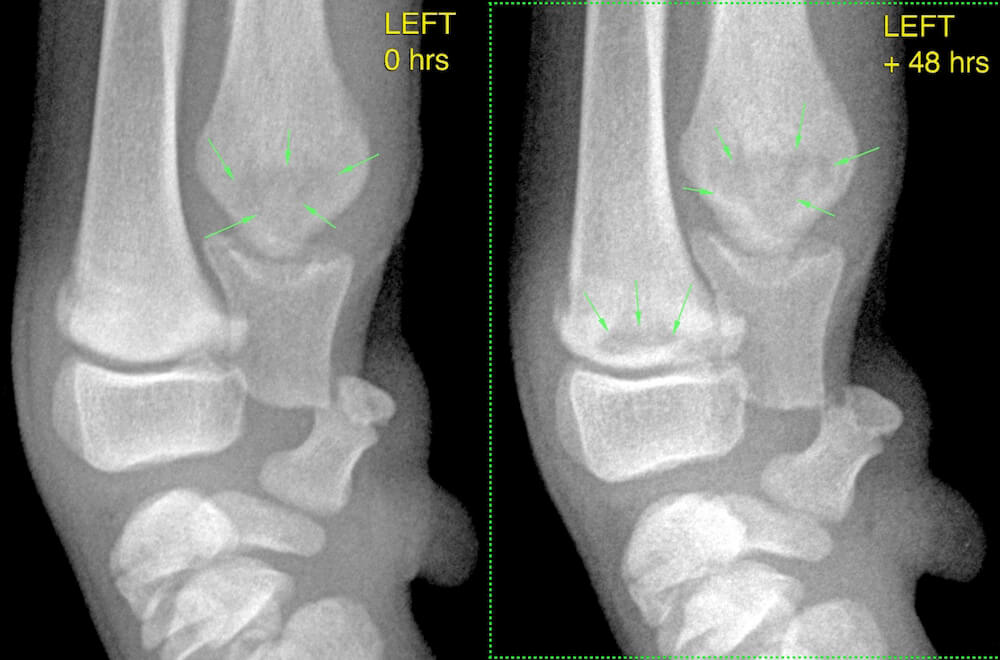

Mediolateral views of the left carpus at Zero hours (presentation) and +48 hours are shown: note how quickly the radiographic appearance can change, highlighting the importance of re-radiographing two to three days later if there is doubt over the initial diagnosis.

Zero hours: irregular radiolucencies are visible in the ulnar metaphysis (green arrows).

48 hours: radiolucencies in the ulnar are much more prominent (green arrows). A somewhat linear lucency has developed in the metaphysis of the radius parallel to the physis (green arrows).